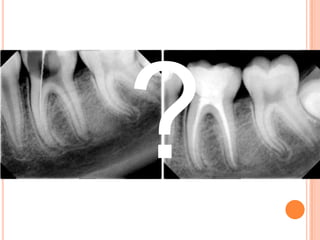

EFECTOS SOBRE LAS RAÍCES Remodelación osea  Remodelación de cemento  Remodelación de dentina  Agresión/reparación  Pérdida permanente?

CAMBIO MEDIO DELONGITUD EN TX CON EXTRACCIONES DE PREMOLARES superior Inferior 1 -2,0 -1,0 2 -2,5 -1,5 3 -1,5 -1,0 5 -1,5 -1,5 6 -1,0 -1,5 7 0 -1,5  Adaptado de Kennedy DB et al: AJODO 84: 183.

 Pérdida deestructura radicular es mínima  SEVERO:1/3 o 50% de pérdida  Propensión individual  Indicios previos  Desequilibrios hormonales y trastornos metabólicos  Ápices puntiagudos  Dilaceraciones  traumatismos

Factores de tratamiento:  Mal control de FF  Tx prolongados  Contacto de hueso cortical  CASOS DE CAMUFLAJE